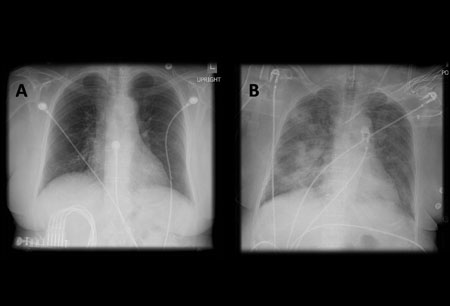

Chest x-ray

A chest x-ray should be obtained early in the evaluation of chronic cough.[38] Although it is not diagnostic of the most common causes, findings may quickly divert the evaluation to causes of greater gravity, such as structural lung diseases. These include lung cancer, pulmonary fibrosis, tuberculosis, bronchiectasis, pneumonia, aspiration, and sarcoidosis.[Figure caption and citation for the preceding image starts]: Chest x-ray showing hyperinflation in a patient with COPD. The hyperinflation is caused by the emphysema component of COPD, rather than the chronic bronchitis that underlies symptoms of coughFrom the personal collection of Dr M. A. Sharifabadand, SUNY at Stony Brook School of Medicine, Department of Pulmonary and Critical Care Medicine, Mineola, New York and Dr J. P. Parsons, The Ohio State University Medical Center, Columbus; used with permission [Citation ends].com.bmj.content.model.assessment.Caption@65a65855[Figure caption and citation for the preceding image starts]: Chest x-ray showing multiple miliary lung metastases (arrows). The primary tumour was a thyroid carcinomaE. Dick, Student BMJ. 2001;9:10-12 [Citation ends].com.bmj.content.model.assessment.Caption@25657fee[Figure caption and citation for the preceding image starts]: Chest x-ray showing left hilar carcinoma (arrow)From: E. Dick, Student BMJ. 2000;8:358-360 [Citation ends].com.bmj.content.model.assessment.Caption@567b9fef[Figure caption and citation for the preceding image starts]: Chest x-ray showing a cavitating right hilar carcinoma (arrow)E. Dick, Student BMJ. 2001;9:10-12 [Citation ends].com.bmj.content.model.assessment.Caption@3d6fa55[Figure caption and citation for the preceding image starts]: Chest x-ray in a patient with bronchogenic carcinoma showing a left-sided pleural effusionFrom: R. Thakkar, Student BMJ. 2001;9:458 [Citation ends].com.bmj.content.model.assessment.Caption@5b46acec[Figure caption and citation for the preceding image starts]: Chest x-ray showing interstitial fibrosis in a patient with amiodarone pulmonary toxicityFrom the personal collection of Dr A. Pataka and Professor P. Argyropoulou, Aristotle University, Thessaloniki, Greece; used with permission [Citation ends].com.bmj.content.model.assessment.Caption@2c3c94b0[Figure caption and citation for the preceding image starts]: Chest x-ray showing pulmonary tuberculosis with cavitationFrom the personal collection of Dr M. Narita, Department of Pulmonary and Critical Care Medicine, University of Washington [Citation ends].com.bmj.content.model.assessment.Caption@3dd7f84b[Figure caption and citation for the preceding image starts]: Chest x-ray showing multiple discrete nodules throughout both lungs (one of which is circled) in a patient with miliary tuberculosisE. Dick, Student BMJ. 2001;9:10-12 [Citation ends].com.bmj.content.model.assessment.Caption@23fa6365[Figure caption and citation for the preceding image starts]: Chest x-ray with lack of normal tapering producing a tram line in a patient with bronchiectasisFrom the personal collection of Dr S.M. Bhorade, University of Chicago Medical Center; used with permission [Citation ends].com.bmj.content.model.assessment.Caption@36b415f2[Figure caption and citation for the preceding image starts]: Chest x-ray with dilated and thickened airways in a patient with bronchiectasisFrom the personal collection of Dr S.M. Bhorade, University of Chicago Medical Center; used with permission [Citation ends].com.bmj.content.model.assessment.Caption@78e208fa[Figure caption and citation for the preceding image starts]: Chest x-ray showing increased opacification of the right perihilar region and superior segment of the right lower and upper lobes consistent with worsening aspiration pneumoniaFrom the personal collection of Dr R. Kanner, University of Utah School of Medicine [Citation ends].com.bmj.content.model.assessment.Caption@71be2c1f[Figure caption and citation for the preceding image starts]: Portable chest x-ray with bibasilar opacities, worse on the right than the left, in a patient with hospital-acquired pneumoniaFrom the personal collection of Dr F. W. Arnold, Division of Infectious Diseases, Department of Medicine, University of Louisville School of Medicine [Citation ends].com.bmj.content.model.assessment.Caption@2c704497[Figure caption and citation for the preceding image starts]: Chest x-ray showing early ill-defined opacities of the right upper lobe above the minor fissure consistent with early changes of aspiration pneumoniaFrom the personal collection of Dr R. Kanner, University of Utah School of Medicine [Citation ends].com.bmj.content.model.assessment.Caption@23fa54d0[Figure caption and citation for the preceding image starts]: A. Portable upright chest x-ray before aspiration; B. Chest x-ray 1 hour after aspiration, showing bilateral diffuse alveolar infiltrates, worse at the bases on the right sideFrom the personal collection of Dr S. Murgu and Dr H. Colt, University of California at Irvine Medical Center [Citation ends].com.bmj.content.model.assessment.Caption@7860be3a[Figure caption and citation for the preceding image starts]: Chest x-ray showing bilateral hilar adenopathy in a patient with sarcoidosisFrom the personal collection of Dr M.P. Muthiah, Division of Pulmonary and Critical Care and Sleep Medicine, University of Tennessee [Citation ends].com.bmj.content.model.assessment.Caption@31e94b4e